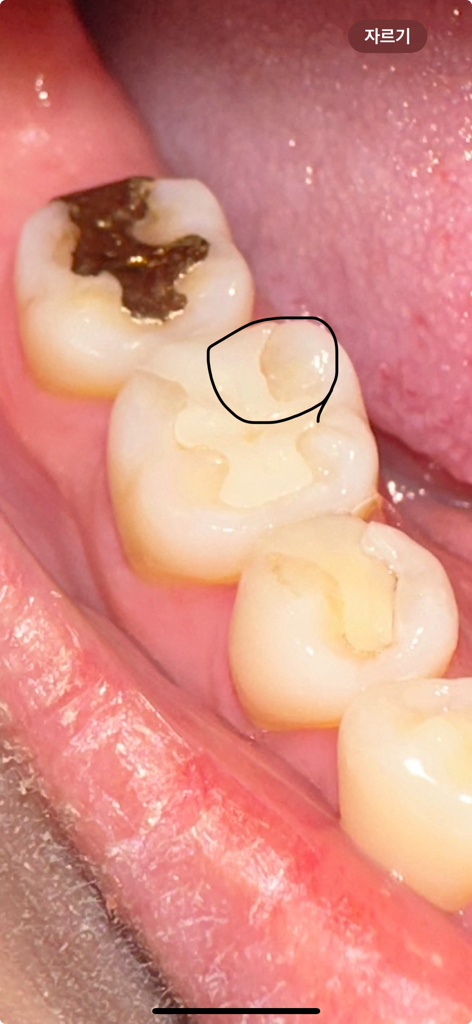

보철물과 치아 틈이 생겼어요 크게 아프거나 불편한건 없지만 나중에 더 안좋아질수도있으니 무조건 보철물 교체를 해야할까요? ㅠㅠ 치과 방문은 금요일에 할 예정입니다.. 혹시 충치가 눈으로만 봐도 보이나요? ㅠㅠ

• 1번 째 사진